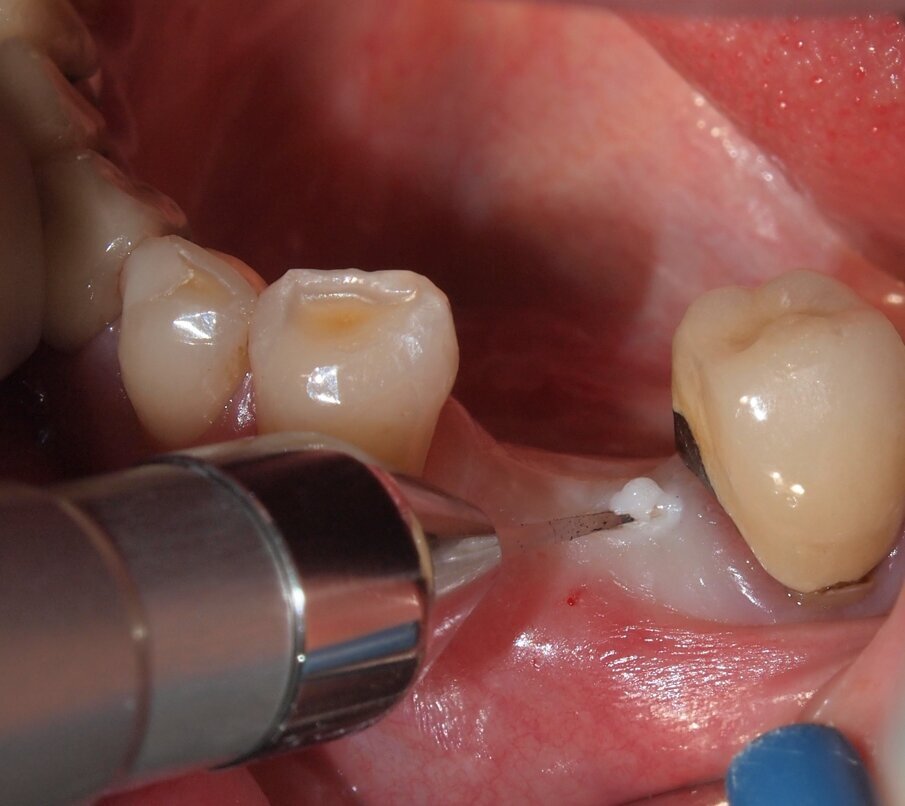

Fig. 3 - Caso clinico 1. Incisione dei tessuti molli con laser a diodi da 915 nm ed inserto in zaffiro. Si osservi l’annerimento della porzione terminale dell’inserto, ad indicarne l’avvenuta attivazione.

Fig. 4 - Caso clinico 1. Incisione dei tessuti molli con laser a diodi da 915 nm e inserto in zaffiro. L’inserto viene condotto lentamente con un movimento simile a quello della lama fredda.

Fig. 5 - Caso clinico 1. Incisione dei tessuti molli con laser a diodi da 915 nm e inserto in zaffiro. Si apprezza macroscopicamente l’assenza di fenomeni di carbonizzazione.